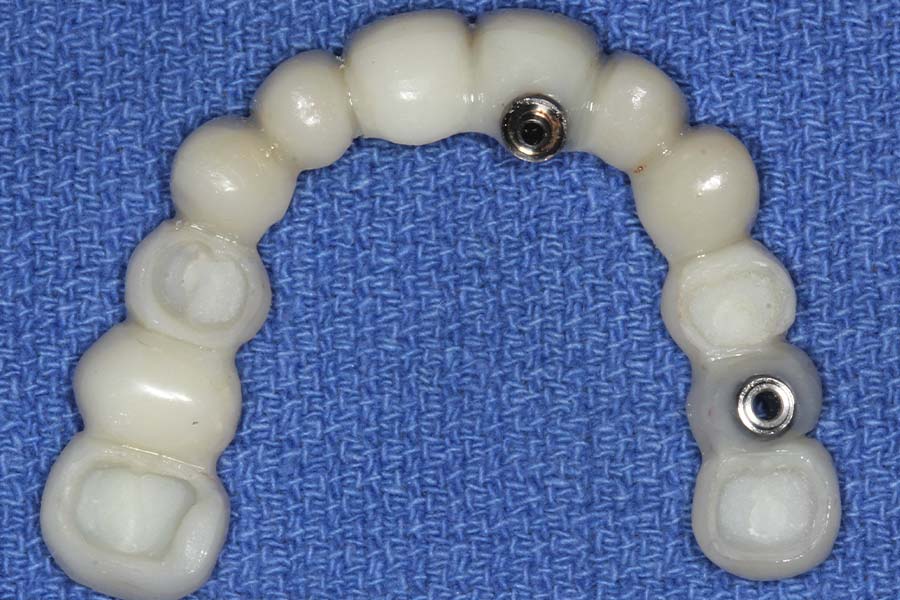

Smile GalleryImplant RestorationsFull Mouth Implant Restoration Full arch zirconia implant bridge (full smile) 1 of 37 Pre-op full smile Pre-op lips retracted Pre-op panoramic x-ray Extraction of strategic teeth Placement of implants Extraction of some remaining teeth after verification of adequate implant stability Occlusal view Post-op panoramic x-ray Immediately fabricated provisional restoration (tissue side view) Immediately fabricated provisional restoration (occlusal side view) Immediate provisional delivered on day of surgery Immediate provisional 2 weeks later Scalloped tissue developed from the provisional at 2 weeks Jig used for making a master impression Provisional in place (full smile) Provisional in place (lips retracted) Provisional in place (right side) Provisional in place (left side) Wax try-in (full smile) Wax try-in (right side full smile) Wax try-in (left side full smile) Wax try-in (full face, lips together) Wax try-in (full smile) Wax try-in (right side) Wax try-in (left side) Wax try-in (lips retracted) Full arch zirconia implant bridge on master cast (frontal view) Full arch zirconia implant bridge on master cast (occlusal view) Implant positions and soft tissue representation on master cast (occlusal view) Soft tissue representation on master cast (frontal view) Full arch zirconia implant bridge (tissue side view) Soft tissues on day of delivery (occlusal view) Soft tissues on day of delivery (frontal view) Full arch zirconia implant bridge delivered (lips retracted) Full arch zirconia implant bridge (lips retracted, close up) Post treatment panoramic x-ray Full arch zirconia implant bridge (full smile)